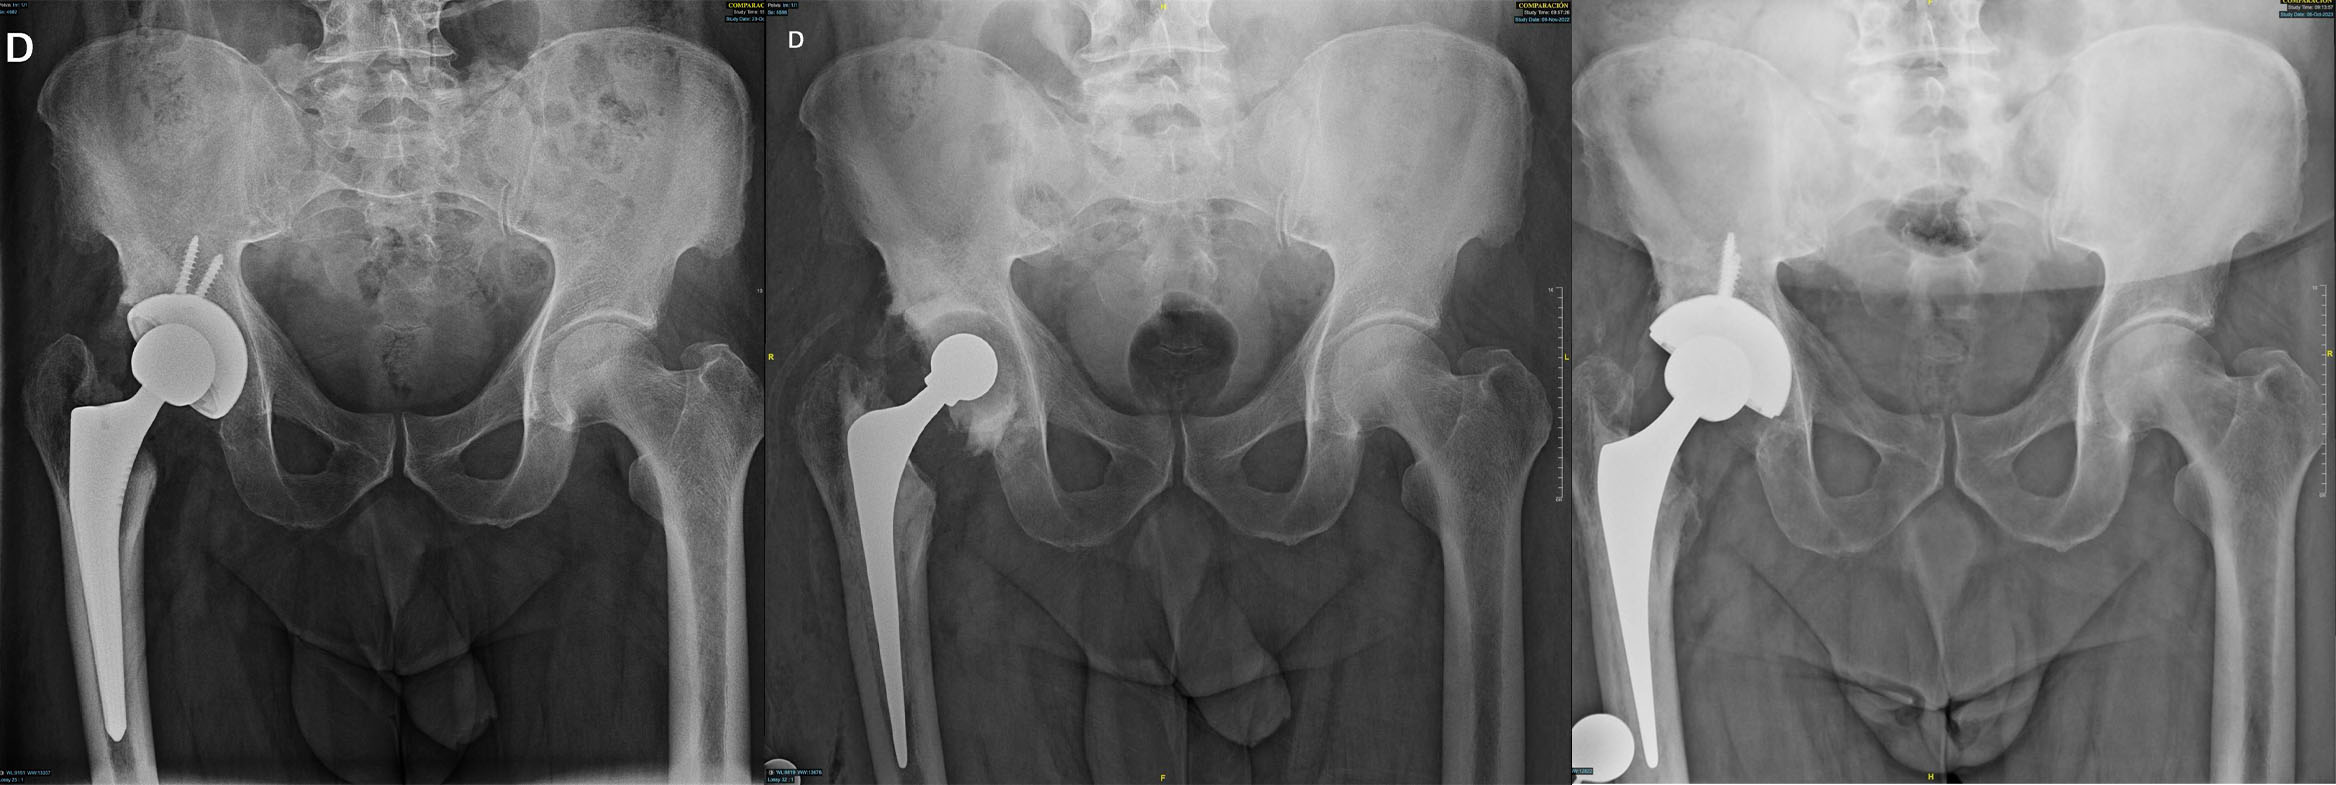

10 Jun Revisión de Prótesis de Cadera por Infección Crónica: Caso Clínico Posted at 03:26h in Blog by admin 0 Comments 0 Likes Antecedentes del Paciente Varón de 53 años, con antecedente de artroplastia... Read More